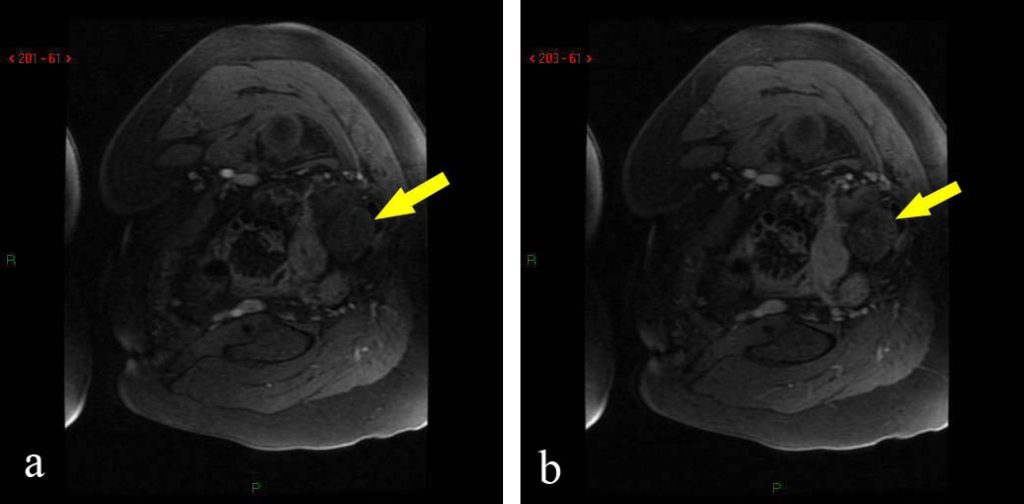

A torção anexial é um evento incomum, porém constitui importante causa de dor abdominal em mulheres. Está frequentemente associada a tumor ou cisto ovariano, mas pode ocorrer em ovários normais, principalmente em crianças. A torção de estruturas anexiais pode envolver o ovário ou a tuba, mas geralmente acomete ambos. Na maioria dos casos, é unilateral, com discreta predileção pelo lado direito. Como achados de imagem, observam-se massas ovarianas e aumento do volume ovariano, com redução ou ausência de sua vascularização. Se a torção for completa e não diagnosticada ou tratada, pode ocorrer necrose hemorrágica, evoluindo com complicações, sendo a peritonite a mais frequente. O diagnóstico precoce ajuda a prevenir danos que são irreversíveis com tratamento conservador, poupando-se o ovário. A limitação do exame físico, a possibilidade de resultados inconclusivos pela ultrassonografia e a exposição à radiação pela tomografia computadorizada fazem da ressonância magnética um complemento valioso na avaliação de emergência das doenças ginecológicas. O objetivo deste trabalho foi relatar dois casos confirmados de torção anexial, enfatizando a contribuição da ressonância magnética no diagnóstico dessa entidade.